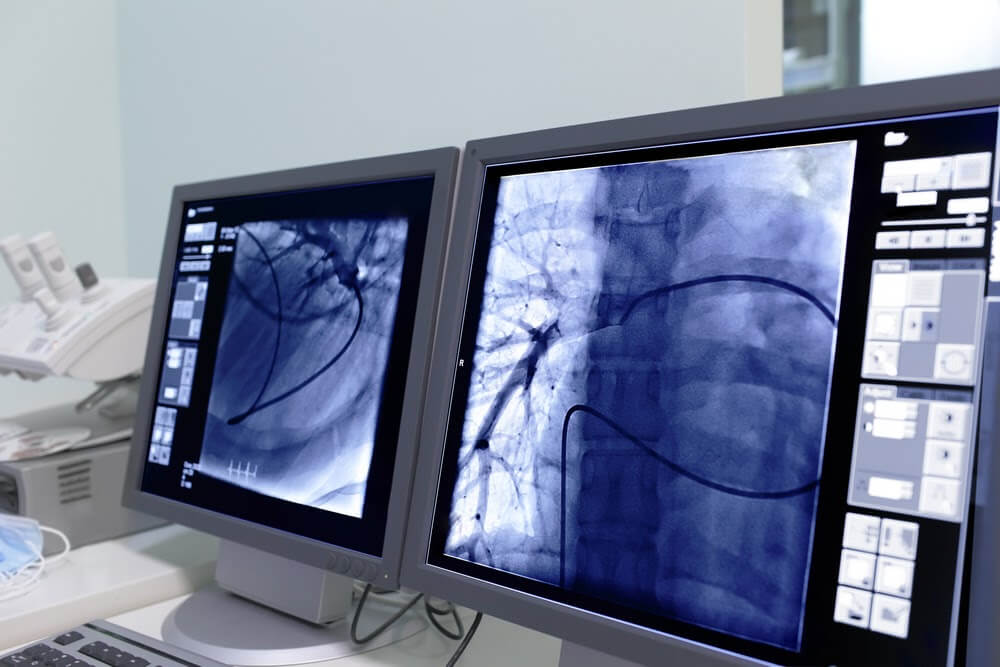

- FluoroscopyÂ

Interventional radiology is one way of treating and diagnosing certain conditions without the need for scopes or surgery. An interventional radiologist is a highly trained professional who has extra training and experience in using imaging technology such as ultrasounds, MRIs and CT scans to guide medical procedures. Interventional radiology is used in treating liver and kidney problems, blockages in arteries or veins, cancers, and back pain. The patient may be awake or mildly sedated during such procedures.Â